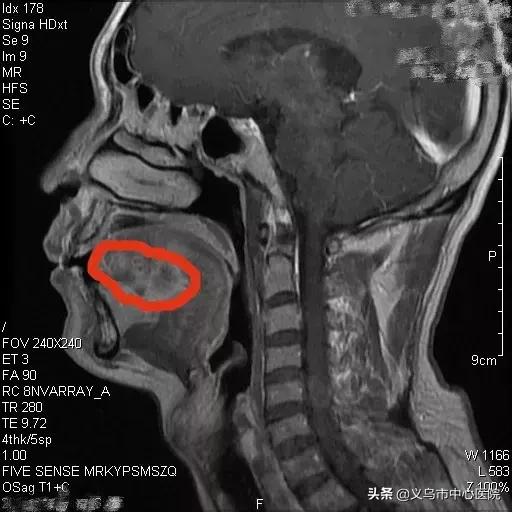

▲ 入院时,磁共振显示王先生的肿瘤范围